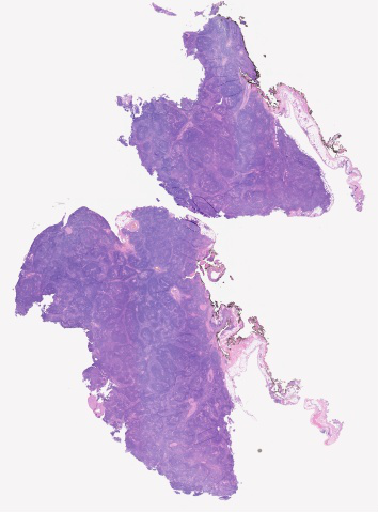

Pathology Image Library

ARUP Laboratories®